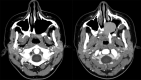

Fig 3.

An 83-year-old woman with sinonasal lymphoma status post chemoradiation therapy, who developed osteoradionecrosis and underwent partial palatectomy and Trusoft obturator placement. A postcontrast CT image shows that the obturator projects into the right nasal cavity (arrow). Foci of air may get trapped in the Trusoft obturator, creating a confusing imaging appearance, which can be mistaken for infection.